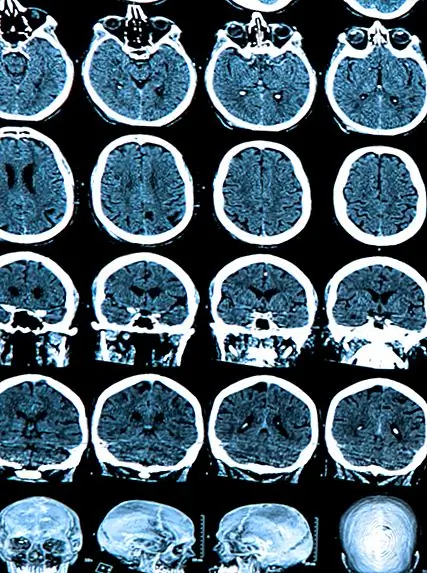

Мозг защищен и снабжен мозговой спинной жидкостью по его желудочковой системе (состоящей из четырех полостей). Одна из этих полостей, третий желудочек, лежит глубоко внутри мозга между двумя половинами таламуса, частью мозга, участвующей в передаче как моторных, так и сенсорных сигналов, и которая играет роль в регулировании сна, сознания и настороженность.

Зная, что Элси страдает от краниофарингиоматозной кисты, которая надавливала на заднюю медиально-вентральную поверхность ее лобной доли, а также стенки третьего желудочка, Кэрнс предложил облегчить давление, слив кисту. После первой процедуры Элси некоторое время улучшилась и, что интересно, не помнила о ее провале. К сожалению, когда киста заполнилась снова, ее симптомы вернулись. Процедура дренирования повторялась дважды, и каждый раз она улучшалась, а затем снова возвращалась в свое прежнее состояние, возникающее без сна, но с минимальным сознанием.